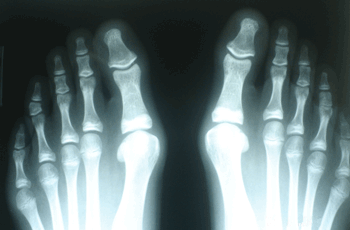

INDICACIONES

Hallux Valgus del Adolescente

Haga click para agrandar las imágenes